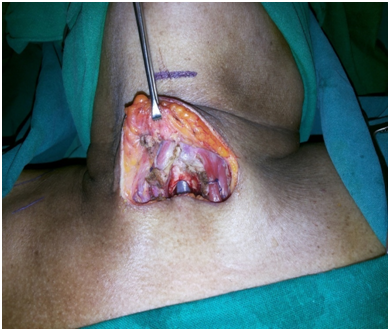

After identifying the landmarks (Figure 5) the neck was explored by a transverse 6 cm incision just on the upper border of the felt pulsation of the vessel. Skin, fat and platysmal incised and upper flap was raised to expose the investing layer of cervical fascia. The lower flap was deliberately not raised to prevent exposing the vessel. This fascia was split in the midline to expose the strap muscles and the isthmus of thyroid gland (Figure 6). The isthmus was split in midline and the edges transfixed to the ipsilateral Sternothyroid muscles (Figure 7). Both sides Sternohyoid muscles were cut at their upper ends, rotated and sutured to the other side (Figures 8&9) sternothyroids making a muscular bed over the horizontally running brachiocephalic trunk just underneath. An inverted “U” flap on the exposed 2nd to 4th tracheal rings was incised and was sutured to the unraised subcutaneous layer of the lower skin flap overlying the vessel hence forming another barrier and a bed for the tracheostomy tube so that it does not rub against it any of the time (Figure 10). Skin incision was closed leaving the opening for the trachoestoma. Portex cuffed tracheostomy tube with suction aid inserted after withdrawing the endotracheal tube.

Figure 8 Strap muscle flaps raised

Figure 9 Strap Muscle Flap Bed

Figure 10 Inverted 'U' Flap Tracheostomy